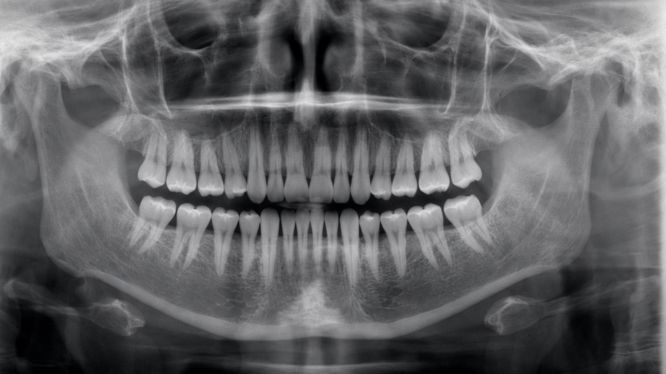

📸 Primero lo primero: ¿Qué es una radiografía panorámica?

La radiografía panorámica es un estudio de imagen que captura en una sola toma:

✔️ Ambas arcadas dentales

✔️ Mandíbula y maxilar

✔️ Articulaciones temporomandibulares

✔️ Senos maxilares

✔️ Estructuras óseas

✔️ Dientes retenidos

✔️ Lesiones ocultas

Es una vista completa del sistema bucal.

A diferencia de las radiografías pequeñas (intraorales), la panorámica muestra TODO el panorama dental (de ahí su nombre).